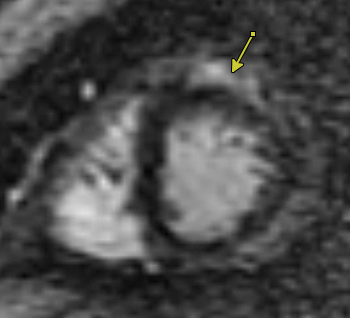

The short Axis LGE demonstrates patchy subepicardial enhancements in the lateral wall of the left ventricle (yellow arrow), consistent with non-ischemic pattern typical of myopericarditis.